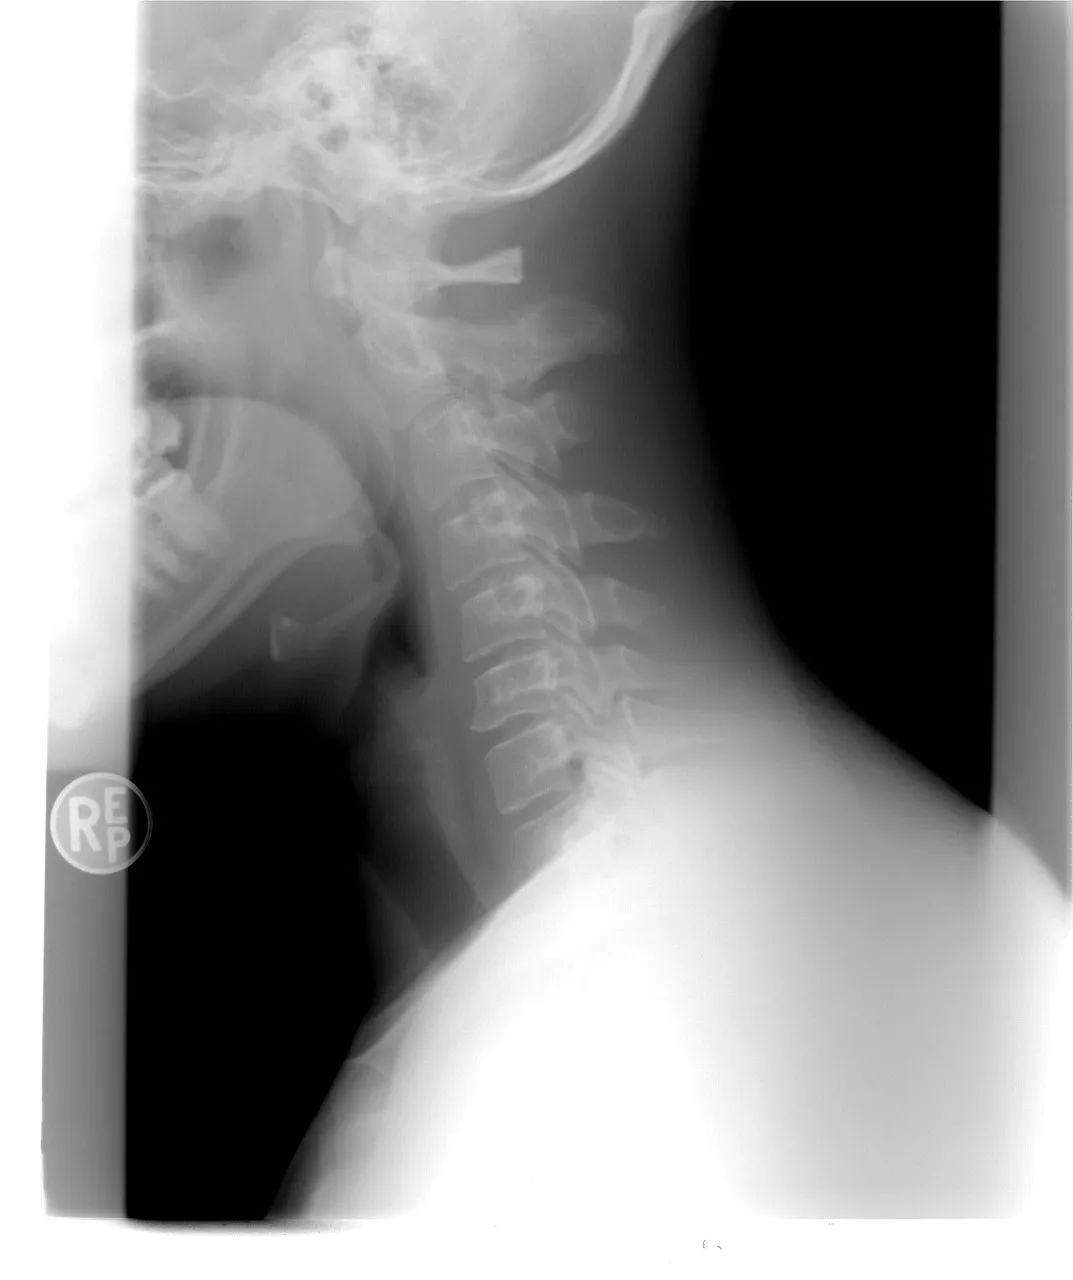

丁俊明是某大厂的软件开发程序员,颈椎病也伴随了他5年之久。27岁那年,丁俊明去医院看颈椎病。经过各项检查后,医生非常严肃地告诉他:“你这颈椎真不像是27岁的啊,像60岁的。”

颈椎X光片。(图/pixabay)检查结果显示,丁俊明的颈椎变形程度已经非常明显,多节椎间盘突出,纤维环已经破裂。医生说如果不及时进行干预,后果不堪设想。这些年,丁俊明忙于工作,实在受不了了才会到医院理疗。他尝试过各种治疗方式,除了颈椎牵引,还做过电针疗法,吃过中药。